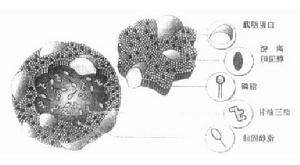

本品為與萬古黴素類似的新糖肽抗生素,其抗菌譜及抗菌活性與萬古黴素相似。對金葡菌的作用比萬古黴素更強,不良反應更少。本品對革蘭陽性菌如葡萄球菌、鏈球菌、腸球菌和大多厭氧性陽性菌敏感。藥效學替考拉寧為一種新型糖肽類非腸道給藥抗生素,具有強的殺菌活性。可供每天一次靜脈或肌肉注射。

青黴菌由於替考拉寧獨特的作用機制,很少出現耐替考拉寧的菌株。所以對青黴素類及頭孢菌素類,大環內酯類、四環素和氯黴素,氨基糖苷類和利福平耐藥的革蘭氏陽性菌,仍對替考拉寧敏感。

藥動學吸收:替考拉寧口服不吸收,肌注後的生物利用度為94%。分布(血清濃度):對人靜注後其血清濃度顯示出兩相的分布(一相快速的分布緊接著是一相較慢的分布),其半衰期分別為0.3和3小時左右。該相分布跟隨一個緩慢的排泄,其半衰期為70-100小時。